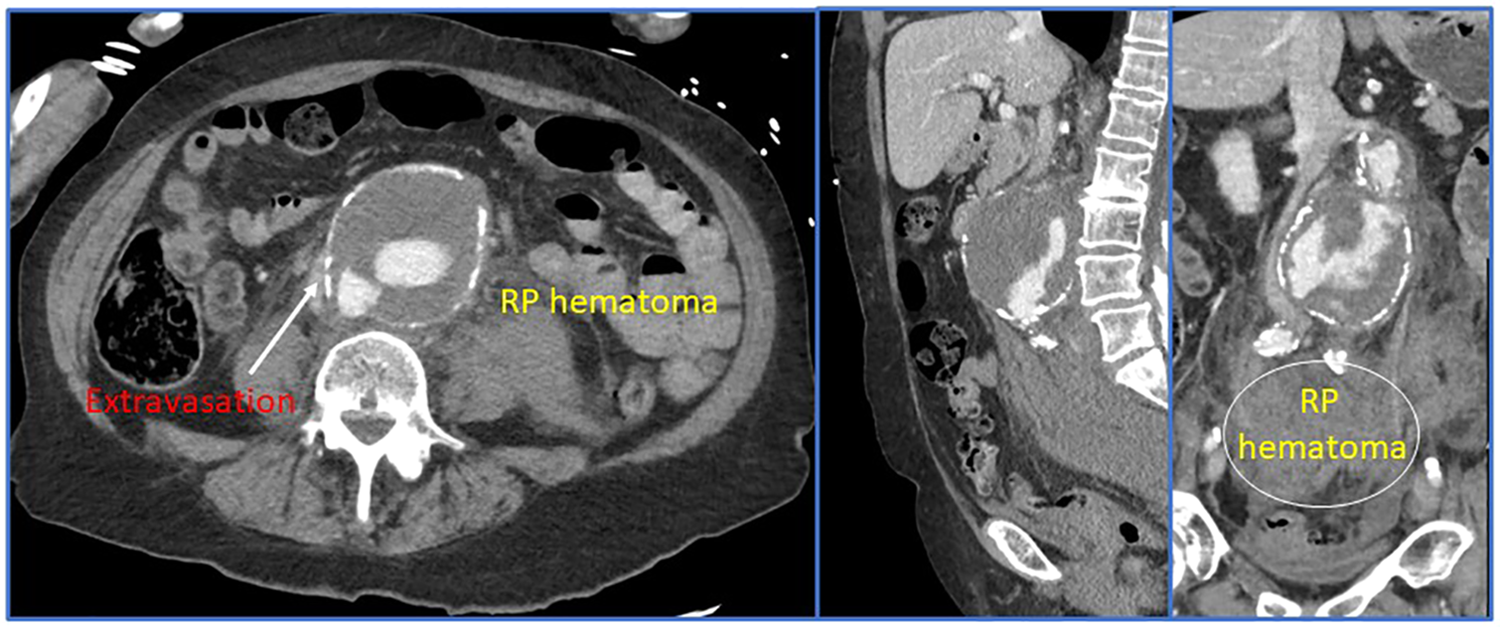

Some of the most important advancements in the modern management of rAAA can be linked to improvements and innovation in preoperative and intraoperative imaging. The gold-standard for imaging is thin-sliced (<1.0 mm) computed tomographic angiography with reformatted images (Figure 3). Most modern healthcare systems across different nations now have access to these scanners and the authors consider it mandatory that patients have a CTA before arrival to the operating room. This remains true even in the hemodynamically unstable patient—since without appropriate imaging, the aneurysm extent, associated morphology, and assessment of the paravisceral aorta would be unknown. Blindly operating on a rAAA that was diagnosed using point-of-care ultrasound is not recommended especially since delineation of relevant anatomic characteristics informs the operating surgeon about the optimal treatment modality and surgical approach (e.g., open vs. endovascular repair; if open, retroperitoneal vs. transperitoneal, etc.). Rapid imaging acquisition times now permit obtaining this vital anatomic information with minimal delay toward operative repair. However, we concede that there are some centers (29) who will allow patients with rAAA to proceed to the operating room without a CT scan and may achieve good results. Irrespective of what imaging bias is employed, an efficient care system is required to ensure timely delivery of the patient to the operating theater.

Figure 3

Preoperative and intraoperative imaging for a ruptured abdominal aortic aneurysm.

Due to the increasing adoption of endovascular techniques to manage the entire spectrum of acute aortic syndromes, many high-volume centers routinely employ three dimensional modeling for rAAA patients using a number of different software platforms (e.g., Siemens Syngo.via®, Osirix™, 3Mensio Vascular®, or TeraRecon, Inc., etc.). Contemporary tertiary aortic referral centers commonly have their own cloud sharing services that allow referring hospitals to rapidly upload images while patients are being transferred. The accepting surgeon can then take these images, generate a 3D-model and determine anatomic eligibility for attempted endovascular repair. Moreover, this designation helps the operating room team so it can set-up the appropriate equipment and instrumentation.